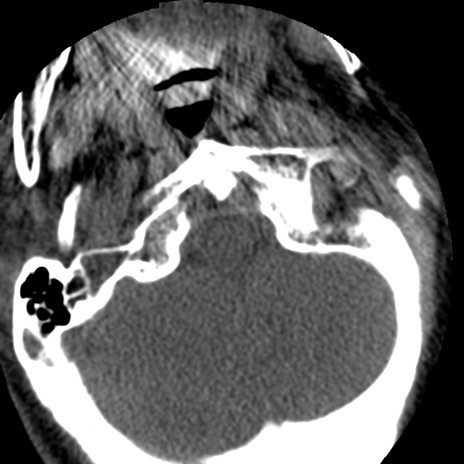

症例50 頚椎CT(横断像)

頚椎CT